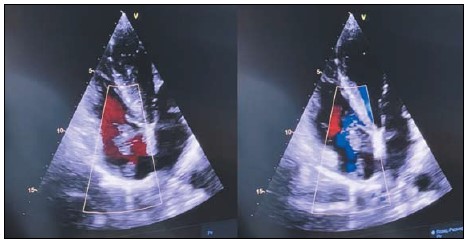

2. Рис. 2. МРТ сердца. Примечание: рисунок выполнен авторами

Тема

Тип Исследовательские инструменты

Посмотреть (38KB)